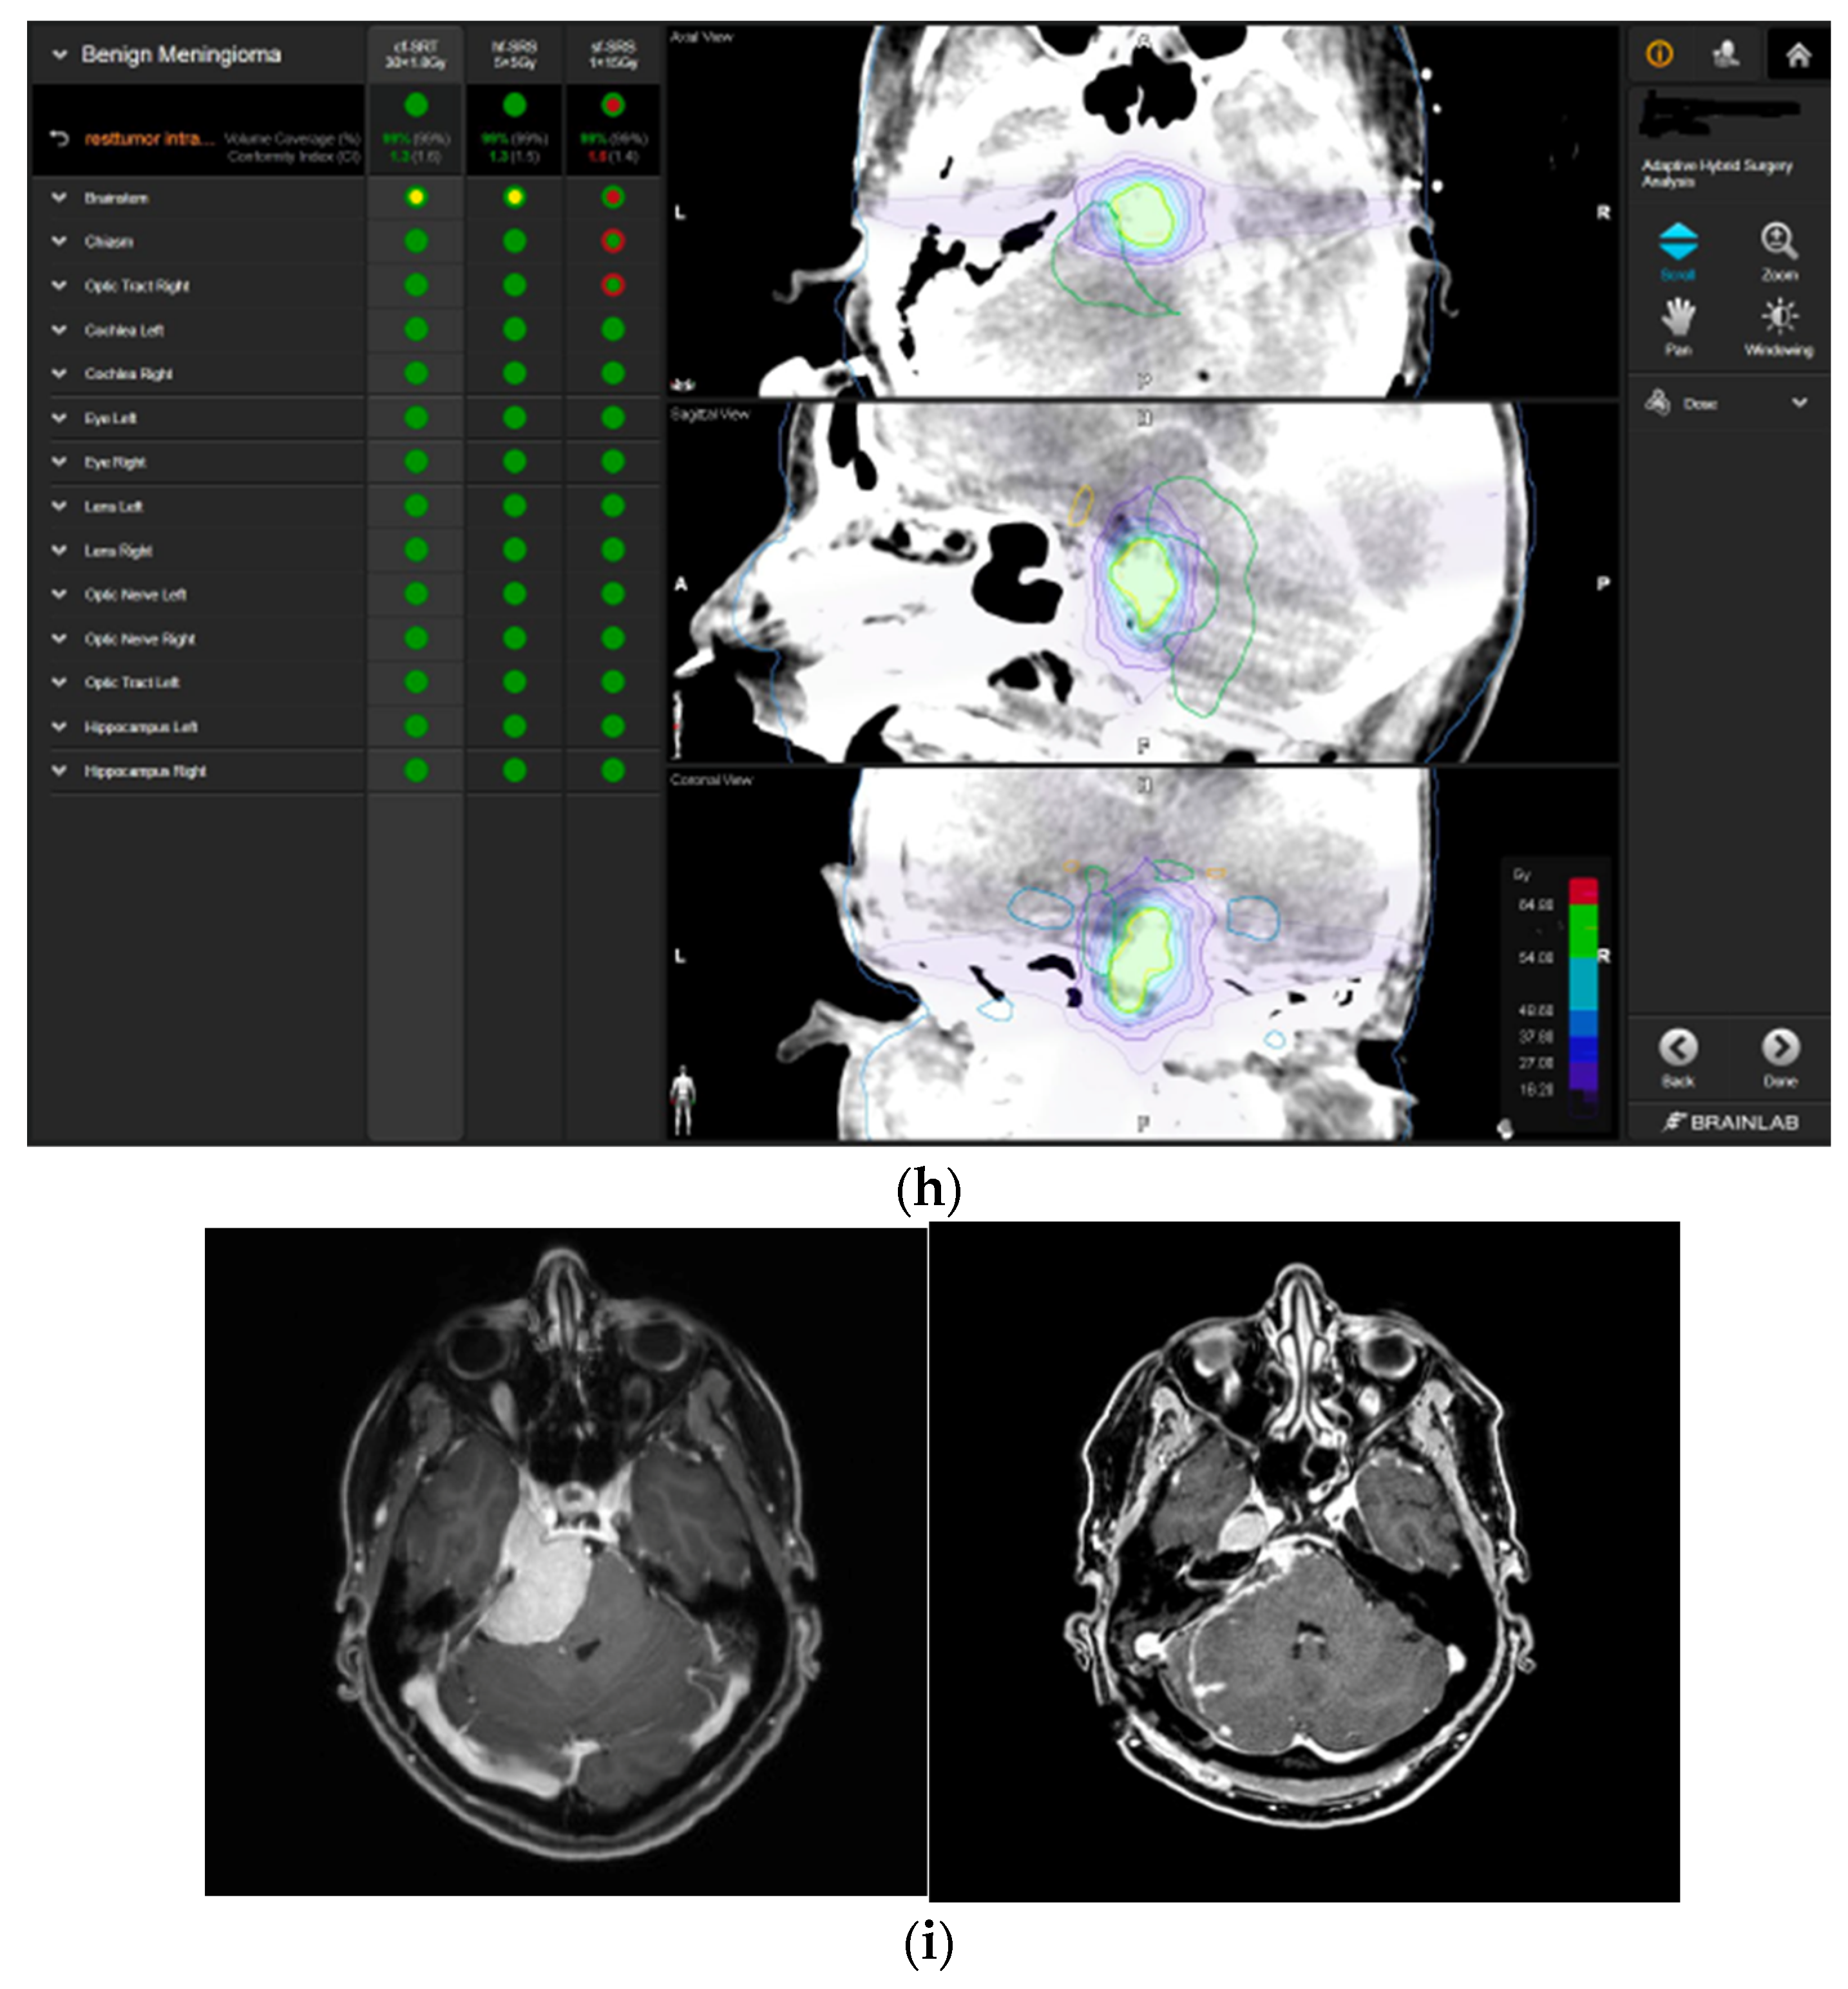

—right hippocampus: unsafe. (g) Overlay of preoperatively estimated and intraoperative effective residual tumor volume in AHSA. (h) Final intraoperative dose constraints after last ISU and data fusion with intraoperative CT. The dose constraints for OARs appeared to improve and were as follows for conventional and hypofractionated radiotherapy:

—brainstem: mean dose is safe, max. dose is marginally safe.

—brainstem: mean dose safe, max. dose unsafe;

—chiasm: mean dose unsafe, max. dose safe;

—right optic tract: mean dose unsafe, max. dose safe. (i) Comparison of pre- and 3 months postoperative MRI for stereotactic radiation planning. The residual tumor was finally treated with hypofractionated radiotherapy (5 × 5 Gy).